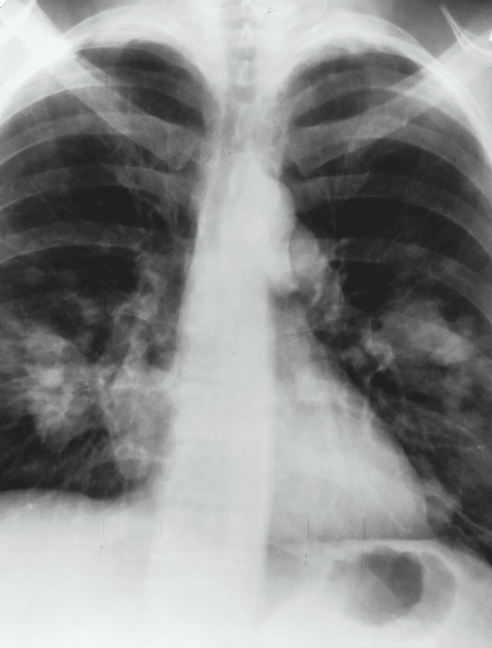

Chest X-ray

• The first step in the diagnostic process is often a chest X-ray.

• Often, a computerized tomography scan (CT scan) of the chest will be used next, although it’s sometimes the first step. A CT scan also uses X-rays but gives doctors a more detailed 3D image.

• Other types of imaging studies may also be used. An MRI uses large magnets to take detailed images, while a PET scan uses a tracer to check for spread of cancer cells throughout the body.